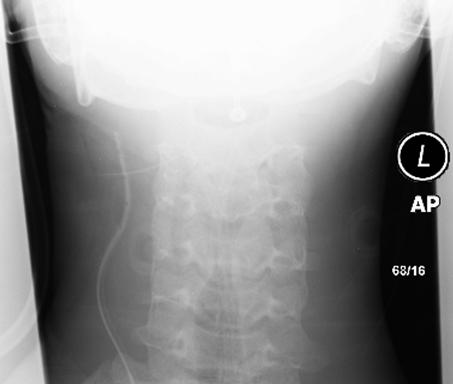

Pneumocephalus - Wikipedia, the free encyclopedia

Pneumocephalus - Wikipedia, the free encyclopedia from upload.wikimedia.org